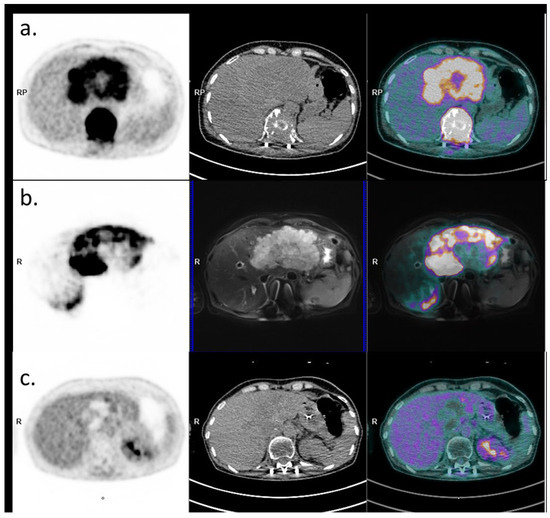

2. Case Presentation